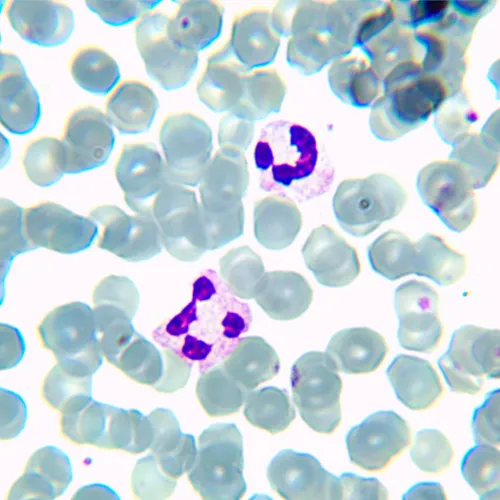

| Назначение | лабораторные/медицинские |

| Метод исследования | светлое поле |

Фотографии в высоком качестве (zip)